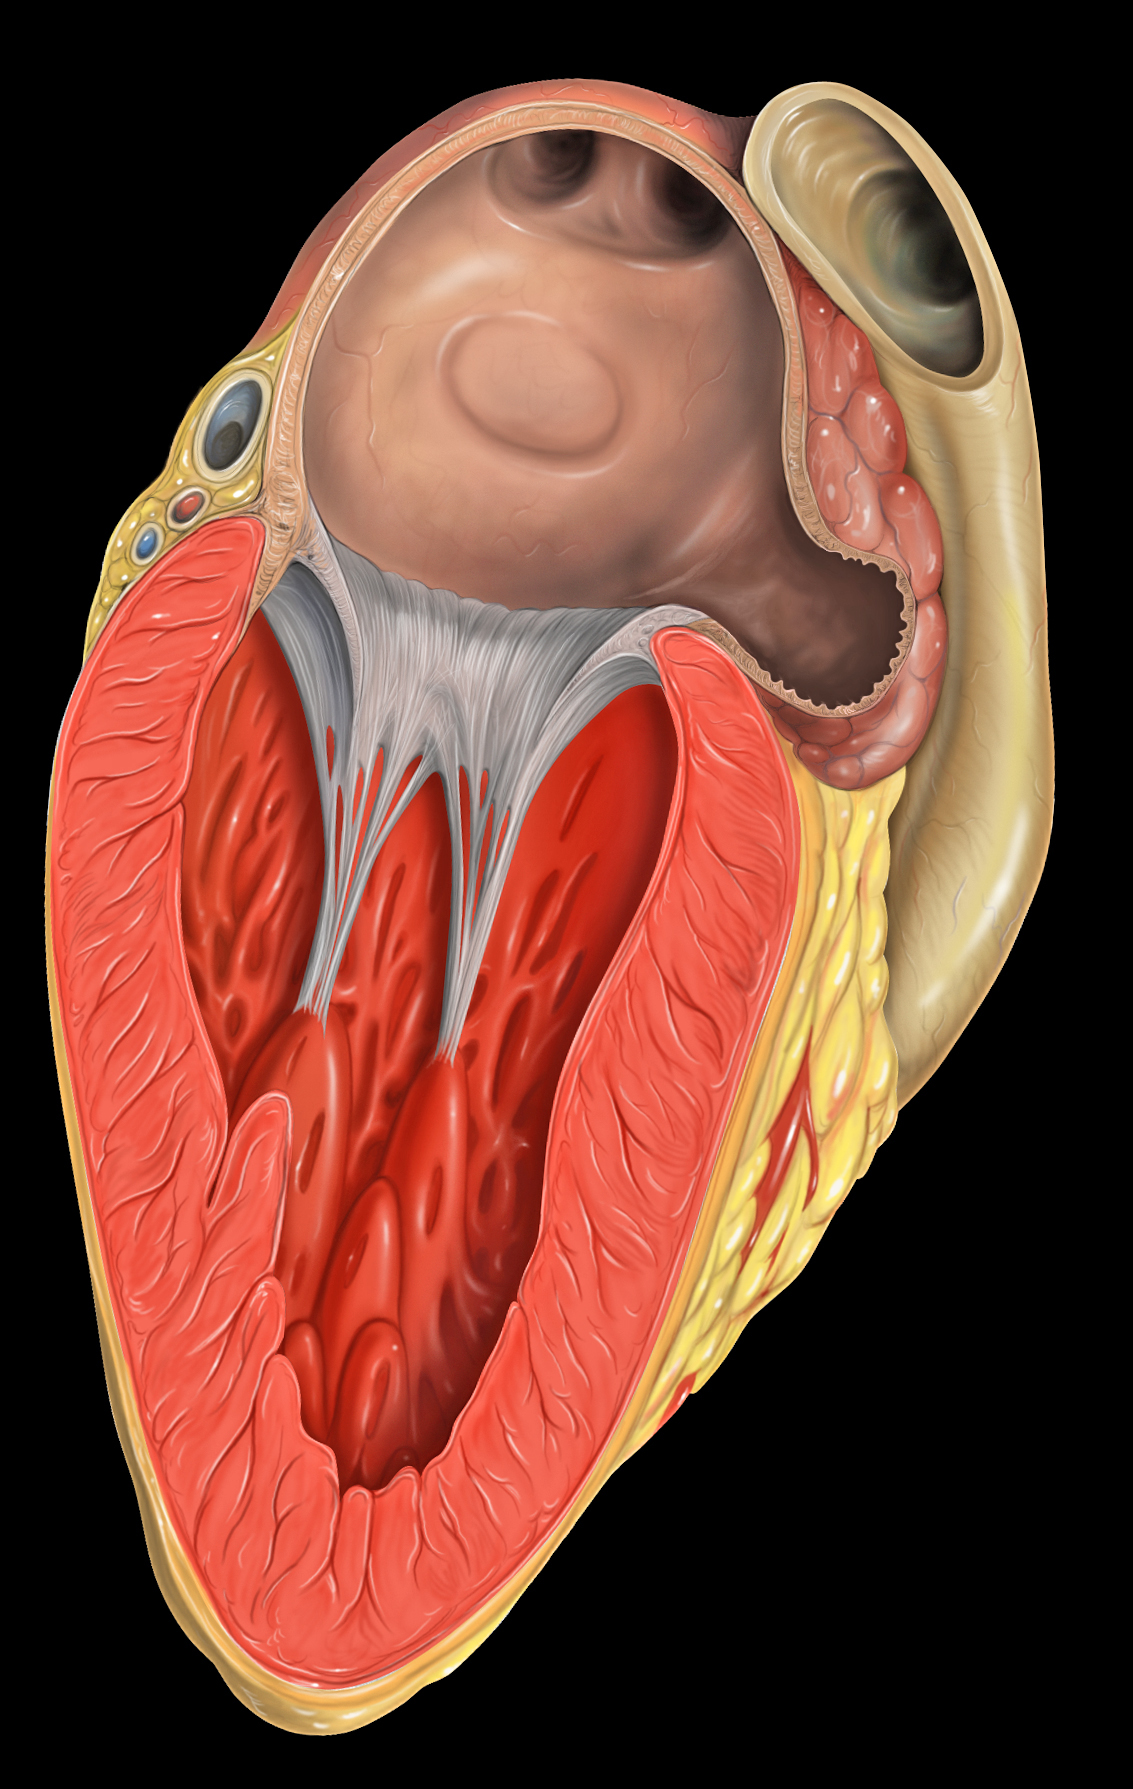

인간의 심장은 우심방, 좌심방, 우심실, 좌심실의 네 개의 방으로 구성되어 있다. 심방은 위쪽에 있는 두 개의 방으로, 혈액을 아래쪽 두 개의 심실로 보낸다.

우심방과 우심실을 합쳐 우심장이라 부르고, 좌심방과 좌심실을 합쳐 좌심장이라고 부른다. 심방에는 입구에 판막이 없기 때문에,[2] 정맥 박동이 정상적으로 나타나며, 경정맥에서 경정맥압으로 확인할 수 있다.[3][4]

내부에는 거친 빗살근과 히스의 결절능선이 있는데, 이는 심방 내부와 우심방의 매끄러운 부분인 ''정맥동''의 경계 역할을 한다. 정맥동은 대정맥과 관상정맥동의 개구부를 둘러싸고 있는 성인의 잔재이다.[5] 각 심방에는 심방 부속지가 붙어 있다.

우심방은 상대정맥, 하대정맥, 전심장정맥, 최소심장정맥, 관상정맥동에서 산소가 제거된 혈액을 받아 삼첨판을 통해 우심실로 보낸다. 우심실은 이를 다시 폐동맥으로 보내 폐순환을 하도록 한다.2. 1. 1. 우심방 부속지

'''우심방 부속지'''는 우심방의 앞쪽 윗부분에 위치하며, 앞에서 보면 쐐기 모양 또는 삼각형 모양으로 보인다. 기저부는 상대정맥을 둘러싸고 있다.[6] 우심방 부속지는 우심방의 주머니 모양 연장부이며 빗살근의 섬유망으로 덮여 있다. 심방 중격은 우심방과 좌심방을 분리하며, 이는 우심방의 함몰 부위인 난원와로 표시된다. 심방은 탈분극에 의해 칼슘이온이 관여한다.2. 2. 좌심방

좌심방은 좌우 폐정맥에서 산소화된 혈액을 받아 승모판 (좌심실판막)을 통해 좌심실로 보내 대동맥을 거쳐 전신 순환으로 펌프질한다.[7][8]2. 2. 1. 좌심방 부속지

3. 심장 전도계

동방 결절(SA node)은 상대 정맥 옆, 우심방 뒤쪽에 위치해 있다. 이곳은 자발적으로 탈분극하여 활동 전위를 생성하는 심장 박동 조율 세포의 집합체이다. 심장 활동 전위는 양쪽 심방 전체로 퍼져나가 수축을 일으키고, 심방이 보유한 혈액을 해당 심실로 밀어 넣는다.

방실 결절(AV node)은 심장 전도계의 또 다른 결절이다. 이곳은 심방과 심실 사이에 위치해 있다.